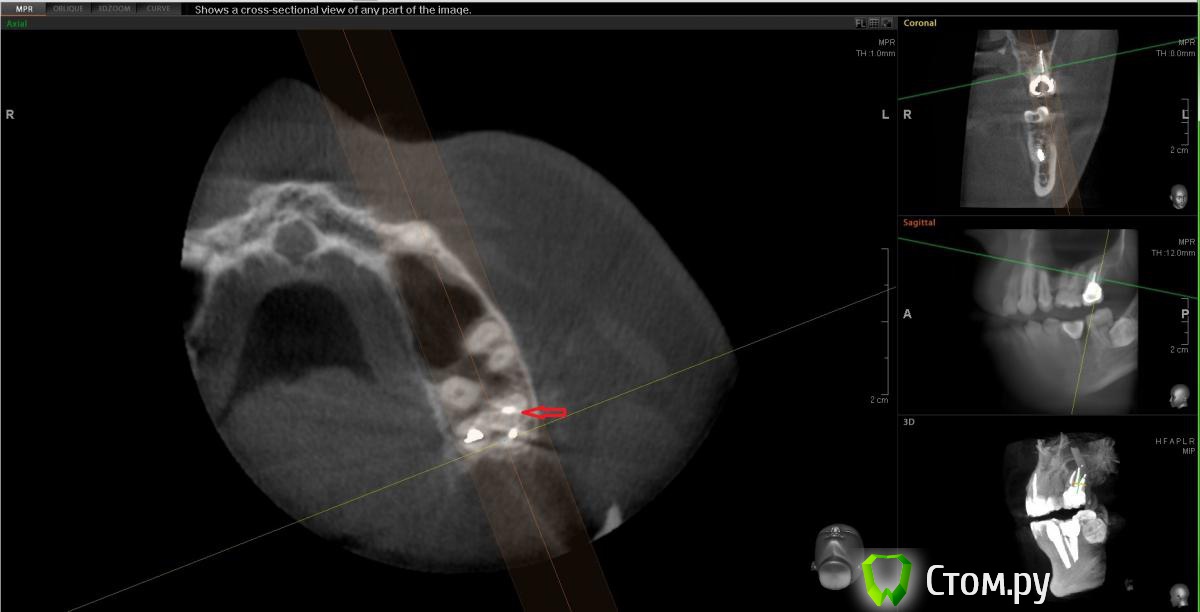

Но оказалось, что это как бы "пора"

post-13796-0-02393600-1400091790.jpg